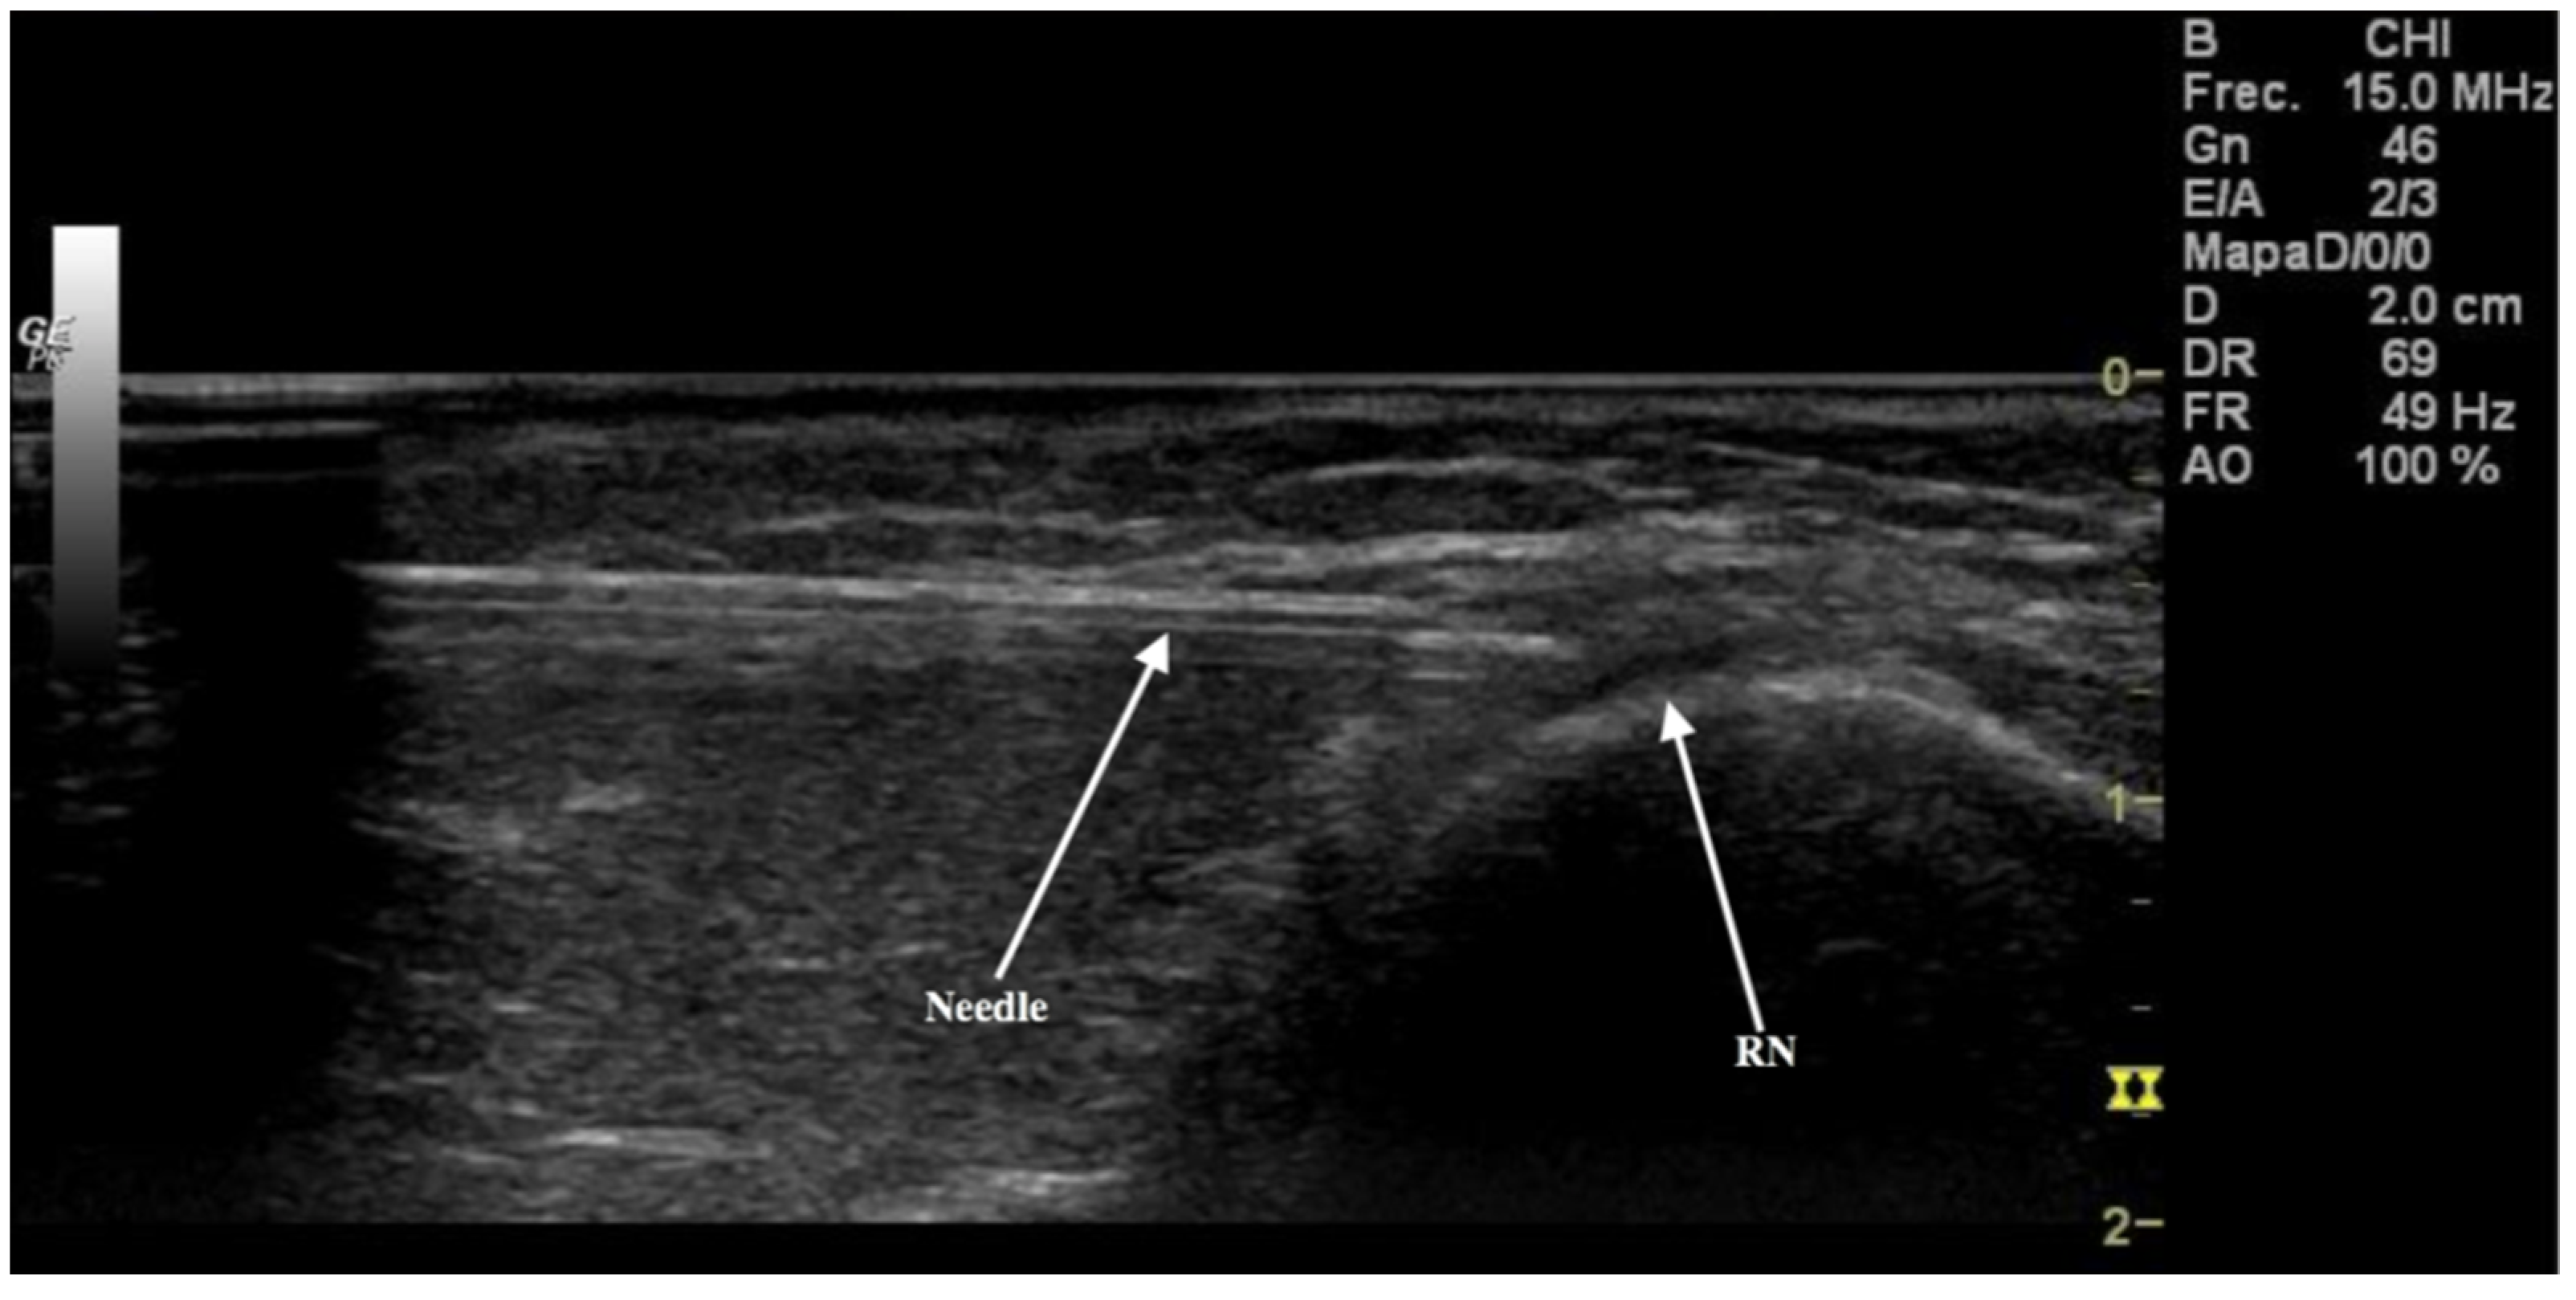

3.1. Ultrasonography Study